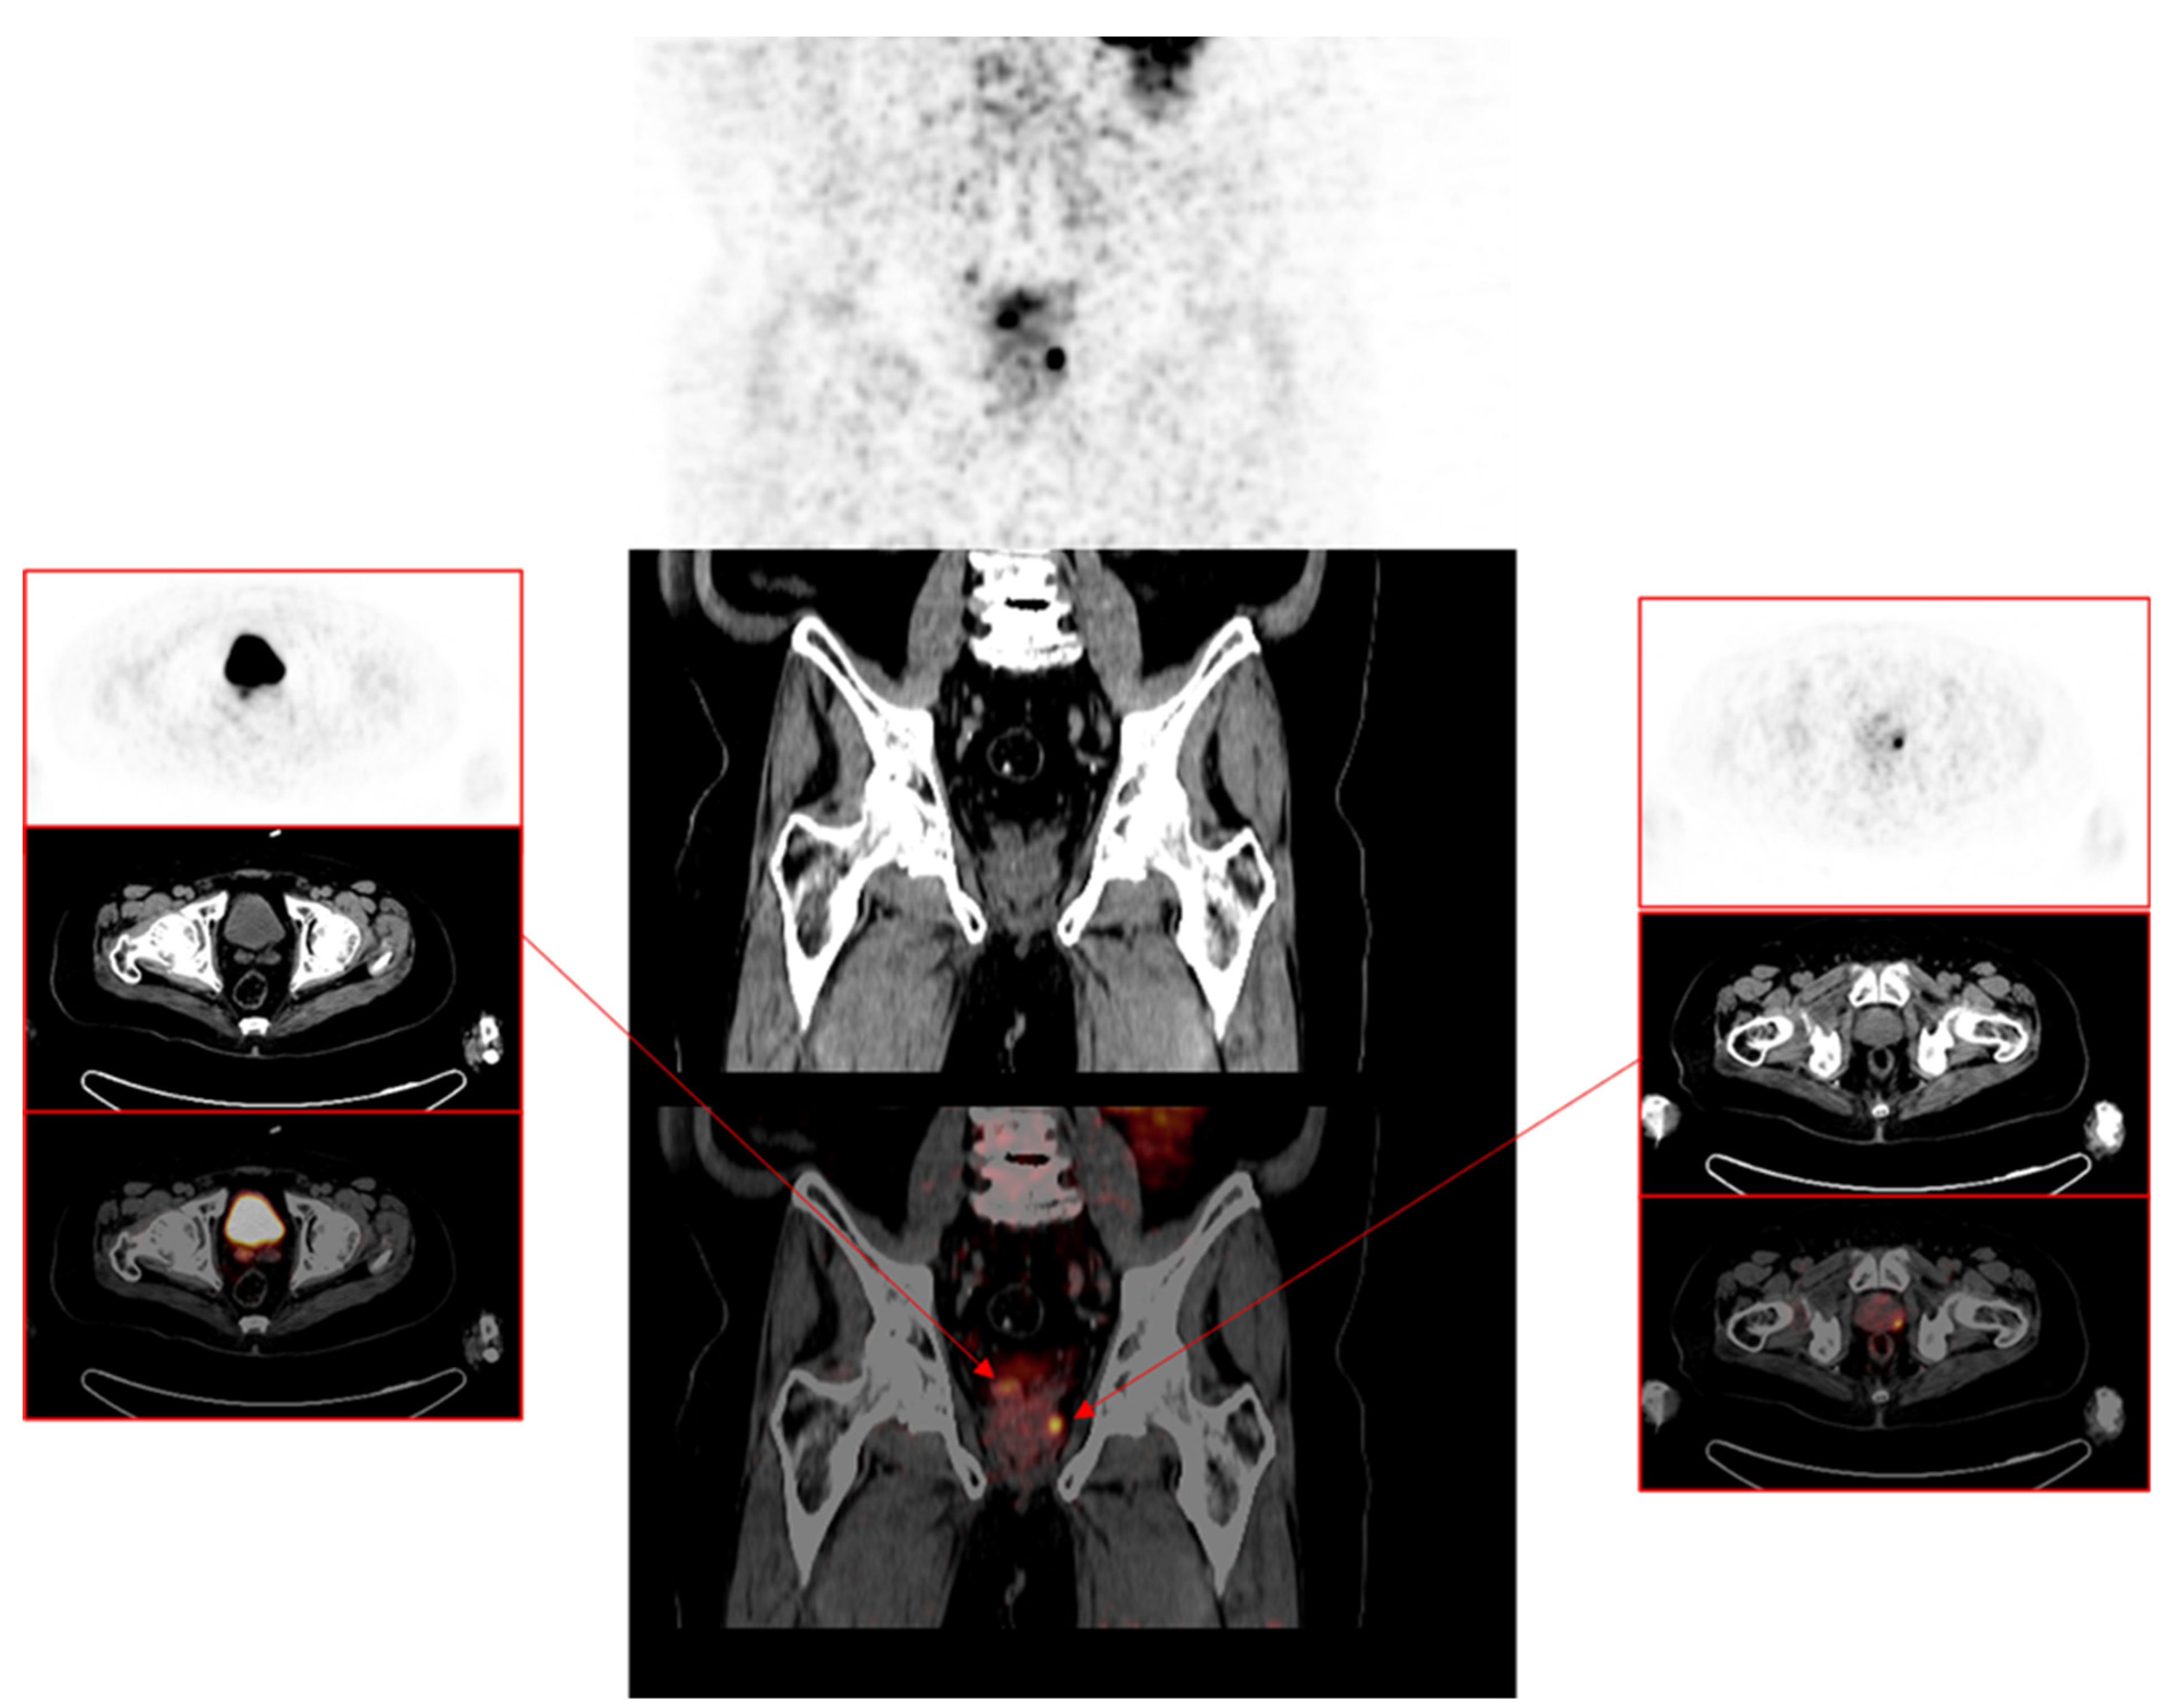

3.1. Pattern of Prostate Cancer Recurrence